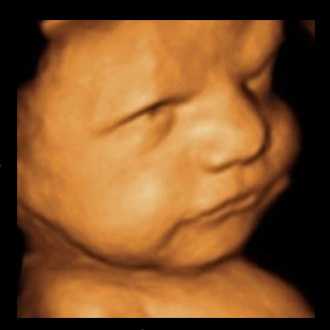

3D/4D SONOGRAPHY

3D/4D SONOGRAPHY (Live)

Built on a digital platform, the Voluson 730 utilizes advanced signal processing technology to ensure optimal image quality for high-resolution 2D, volumetric 3D and real-time 4D imaging. Image quality is further enhanced with Harmonic imaging, spectral, color and Doppler imaging,as well as our latest advance – Compound Resolution Imaging.

• High-resolution 2D, volumetric 3D and real-time 4D imaging